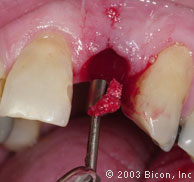

3. | 龋坏的左侧切牙的近观。 |